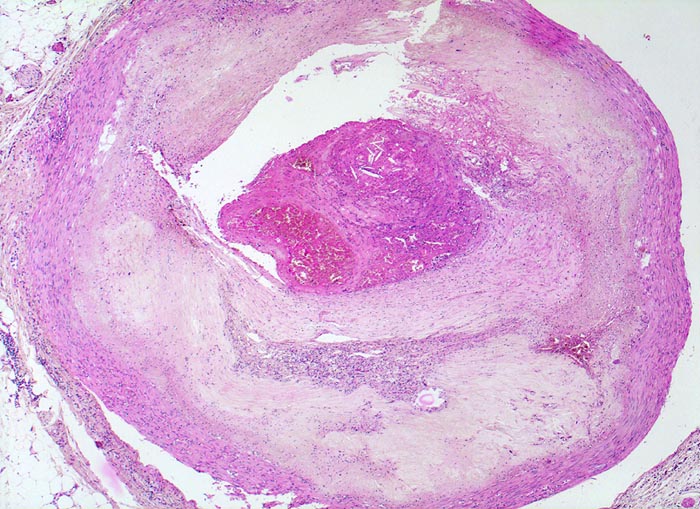

Makroskopisch sind Thromben am besten auf Querschnitten in 3 bis 5mm Abständen durch die Koronargefässe darstellbar. Thromben, die zum Tod des Patienten geführt haben, erkennt man meist makroskopisch. Mikroskopisch findet sich ein Kontinuitätsunterbruch in einer entzündlich veränderten fibrösen Deckplatte über einem Atherom. Dadurch gerät der lipidreiche Kern des Atheroms in Kontakt mit dem luminalen Blutstrom und dies führt zur Ausbildung eines Plättchen-Fibrin Thrombus und zur Einblutung in das Atherom. Meist zeigt der Thrombus Zeichen der beginnenden Organisation. Histologisch ist bei einer Ruptur die denudierte Endotheloberfläche von einem luminalen Thrombus bedeckt.

• Atherom mit fibröser Deckplatte.

• Exzentrische Lumeneinengung durch Verdickung der Intima.

• Organisierender geschichteter Abscheidungsthrombus über Defekt in der fibrösen Deckplatte. Der Thrombus enthält zusätzlich Atherombestandteile (Cholesterinkristalle und nekrotischer Detritus).